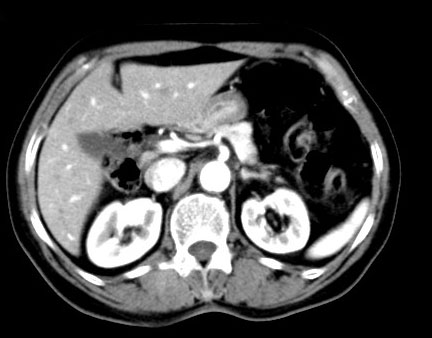

以下是增强:

这例肾病变诊断并不难,我想说的是有时增强很有必要。

平扫:略高密度影,与肾脏分界欠清晰。增强:形态规则,边缘光滑,囊内密度均匀,边缘强化,内部不强化。

考虑:高密度肾囊肿。

鉴别诊断:囊性肾癌。